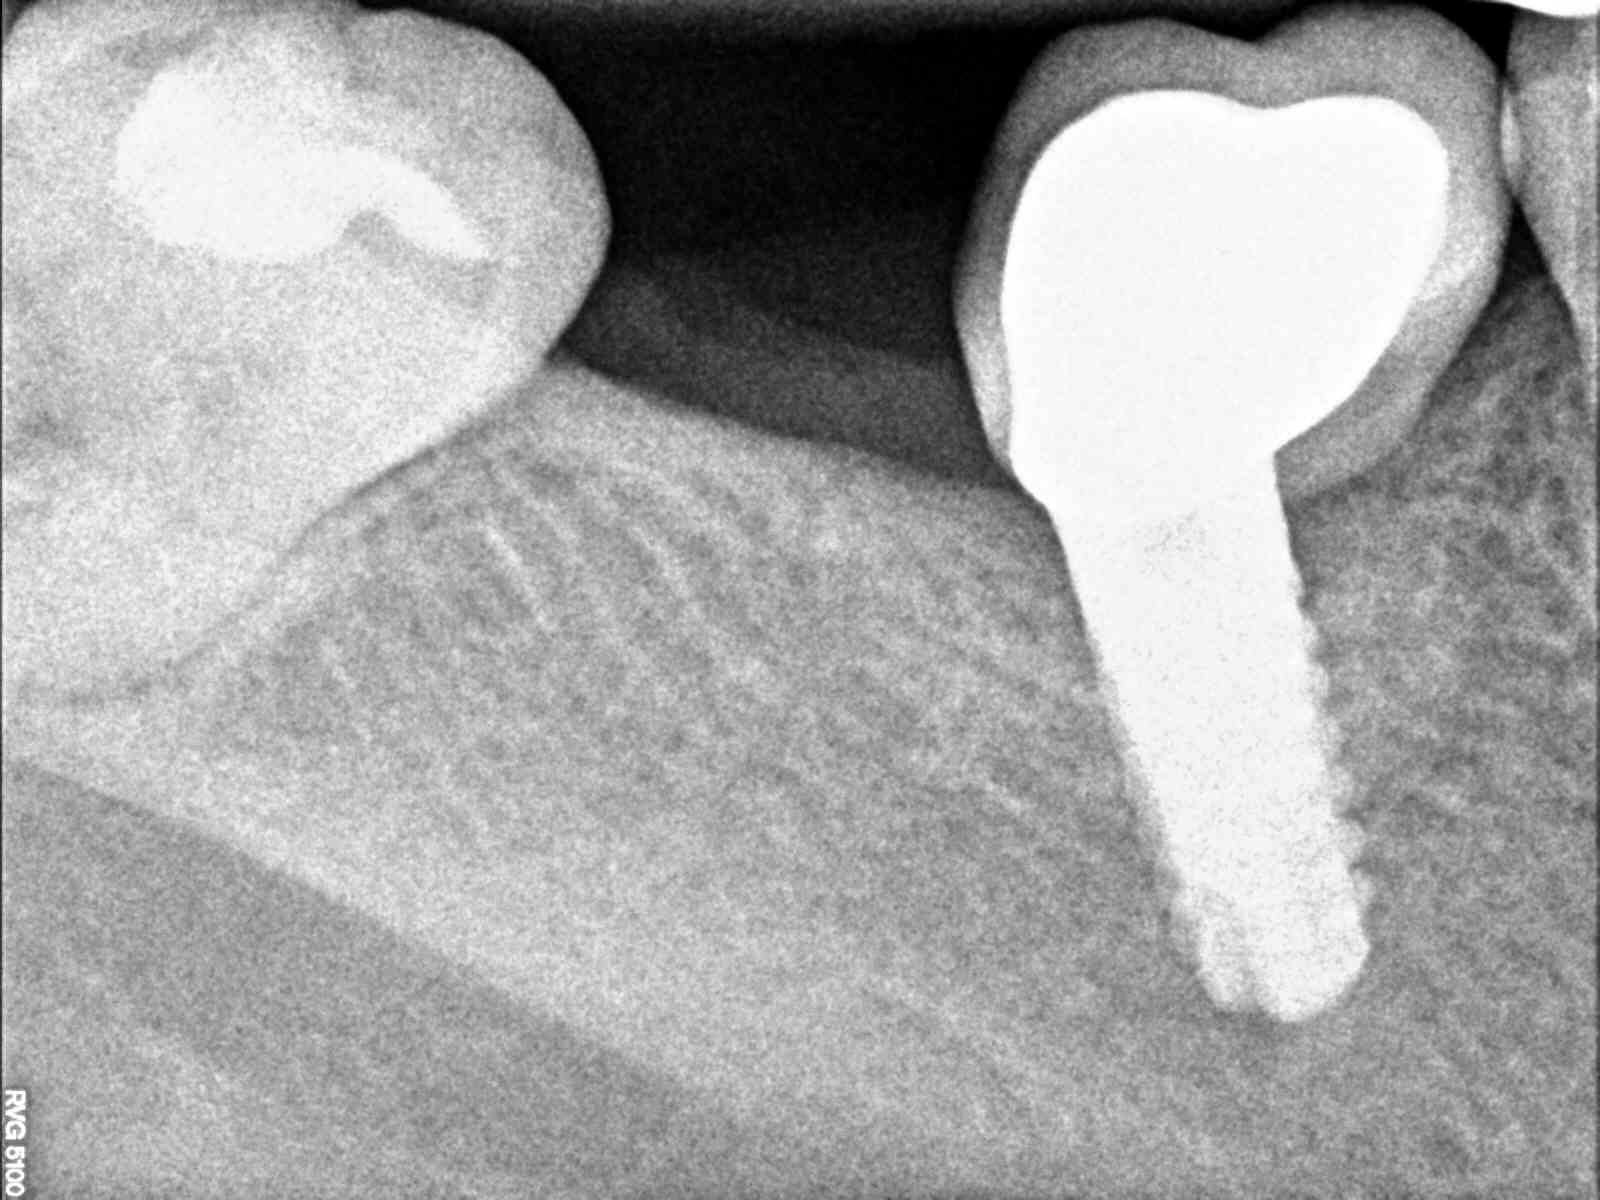

implante desconocido

Hola. Daros las gracias por esta web, me estreno en ella y espero que nos veamos en más ocasiones. Les mando la periapical de un implante que me ha llegado [...]